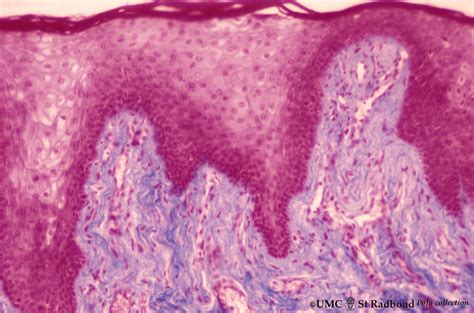

• lip anatomy vermilion border